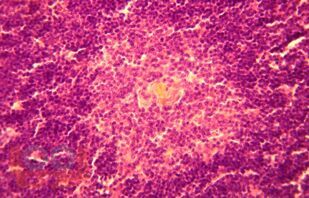

Монография посвящена результатам исследования возрастной морфологии тимуса в условиях воздействия дозированной гиподинамии и гипокинезии, которые можно использовать в различных разделах школьной гигиены, педиатрии, иммунологии, возрастной морфологии, в спортивной медицине.